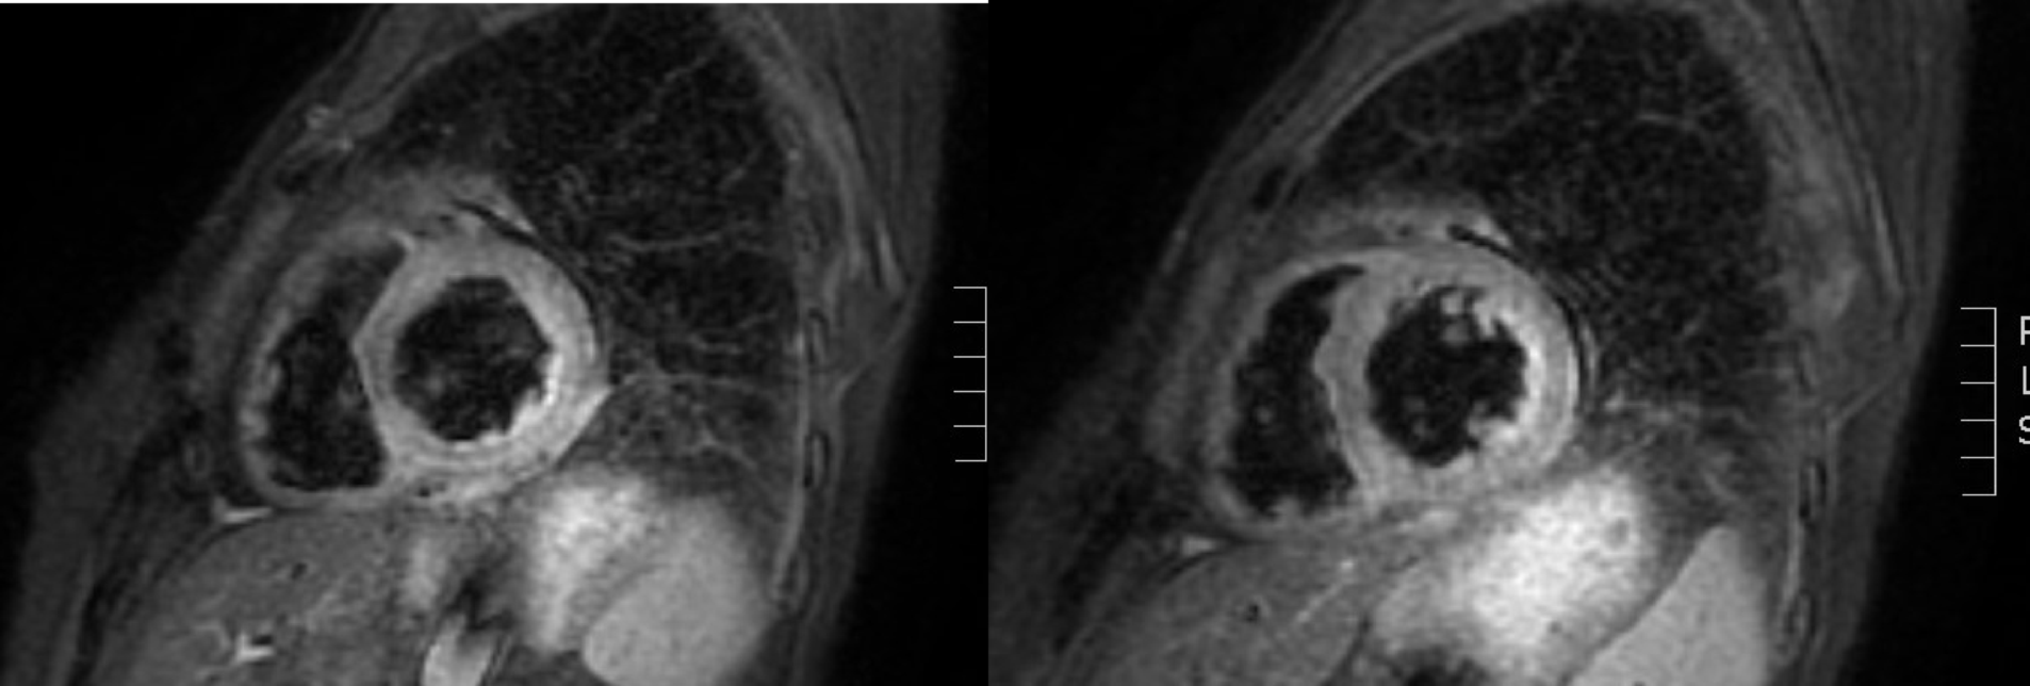

A periumbilical fat biopsy revealed fibroadipose tissue without amyloid deposits at Congo red and thioflavin staining. Cardiac MRI findings were compatible with amyloidosis showing “mid-basal LV, circumferential, subendocardial-transmural late gadolinium enhancement (LGE), more prominent in the inferior and lateral regions” (Fig. 2).

Fig. 2

Cardiac MRI findings showing mid-basal left ventricular LGE in a circumferential, subendocardial-to-transmural pattern, more pronounced in the inferior and lateral regions

The MRI pattern, although not pathognomonic, was highly suggestive of cardiac amyloidosis [6]. Interestingly, right ventricular (RV) endomyocardial biopsy revealed histological findings of replacement fibrosis consistent with SSc, while AL amyloid deposits were detected at electron microscopy (EM). EM of the umbilical fat biopsy confirmed AL amyloidosis (κ light chains).